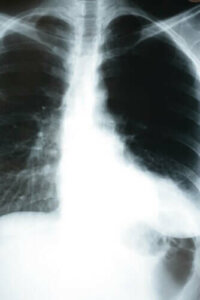

Zatürre akciğerlerin alveollerini etkileyen bir enfeksiyondur. Bunlar, gaz değişimini gerçekleştirmek ile görevli olan küçük, kan damarları ile kaplı keselerdir. Diğer bir deyişle bu keseler karbondioksiti (CO2) dışarıya atmak ve dışarıdan oksijen almak ile sorumludur. Bundan dolayı zatürre vücudu nasıl etkiliyor sorusu çok önemlidir – çünkü bu gaz değişimi çok hayati bir süreçtir.